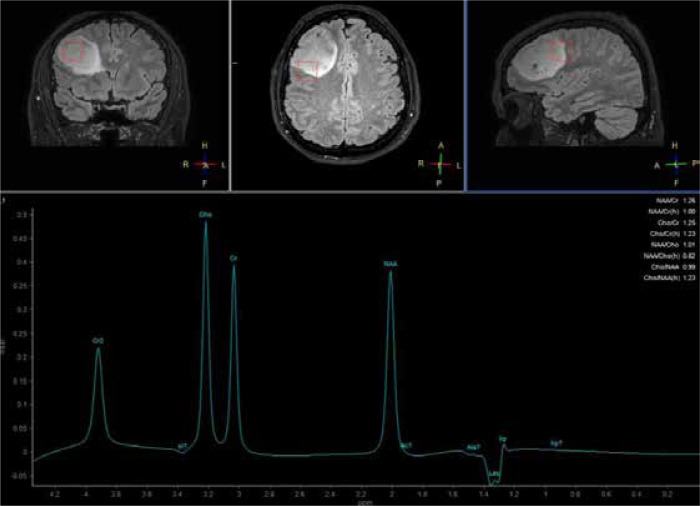

胶质母细胞瘤是成人恶性原发性脑肿瘤中最常见、最具侵袭性的一种。标准治疗方法是手术切除,然后进行放疗和化疗。尽管采用了最佳治疗方法,但患者的预后仍然很差。术前确定胶质母细胞瘤的边缘仍然有利于彻底切除肿瘤。放疗对术后治疗至关重要,但放射抗药性是导致高死亡率的一个重大挑战。先进的成像技术可用于分析瘤周脑区(PTZ)的变化。因此,这些技术可能会开发出新的治疗方案,尤其是针对肿瘤边缘部位的治疗方案,从而改善胶质母细胞瘤患者的预后。胶质母细胞瘤的临床表现多种多样,主要取决于肿瘤的位置和大小。胶质母细胞瘤的特点是瘤内细胞异质性和向肿瘤周围正常组织的广泛、弥漫性浸润(称为 PTZ)。神经成像技术,如弥散加权成像(DWI)、弥散张量成像(DTI)、灌注加权成像(PWI)、质子磁共振波谱(1H MRS)和化学交换饱和转移(CEST)是评估肿瘤浸润和切除边缘的有用方法。

Glioblastomas are the most common and aggressive form of malignant primary brain tumors in adults. The standard treatment is surgical resection followed by radiotherapy and chemotherapy. Despite optimal treatment methods, the prognosis for patients remains poor. Preoperative determination of glioblastoma margins remains beneficial for the complete removal of the tumor mass. Radiotherapy is essential for post-surgery treatment, but radioresistance is a significant challenge contributing to high mortality rates. Advanced imaging technologies are used to analyze the changes in the peritumoral brain zone (PTZ). Consequently, they may lead to the development of novel therapeutic options, especially targeting the marginal parts of a tumor, which could improve the prognosis of glioblastoma patients. The clinical presentation of glioblastoma is heterogeneous and mostly depends on the location and size of a tumor. Glioblastomas are characterized by both intratumoral cellular heterogeneity and an extensive, diffuse infiltration into the normal tissue bordering a tumor called the PTZ. Neuroimaging techniques, such as diffusion-weighted imaging (DWI), diffusion tensor imaging (DTI), perfusion-weighted imaging (PWI), proton magnetic resonance spectroscopy (1H MRS), and chemical exchange saturation transfer (CEST) are useful methods in the evaluation of the tumor infiltration and thus the resection margin.